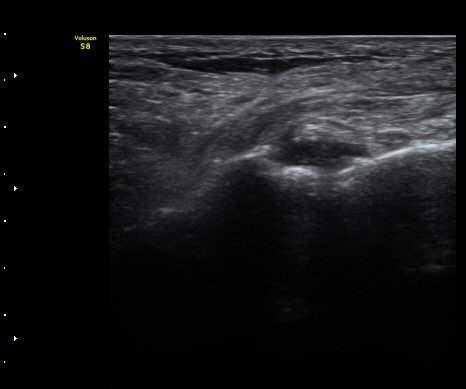

ÃÊÀ½ÆÄ °Ë»ç

Á¾°ñÀÔ¹æ°ñÀδëÀÇ Á¾´Ü¸é°Ë»ç¿¡¼­ ÀδëÀÇ Á¾°ñ ºÎÂøºÎ ÆÄ¿­ÀÌ °üÂûµÊ(»çÁø 1, 2, 3).